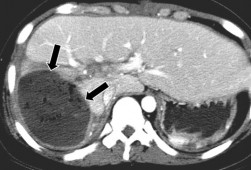

Hình 1.21. CTG độ V. Rách nhu mô gan thùy gan P và thùy gan T.

Hình 1.22. CTG độ V. Vết rách gan sâu, tổn thương vào các TM gan.

Nguồn: Shanmuganathan K, Mirvis SE [21].